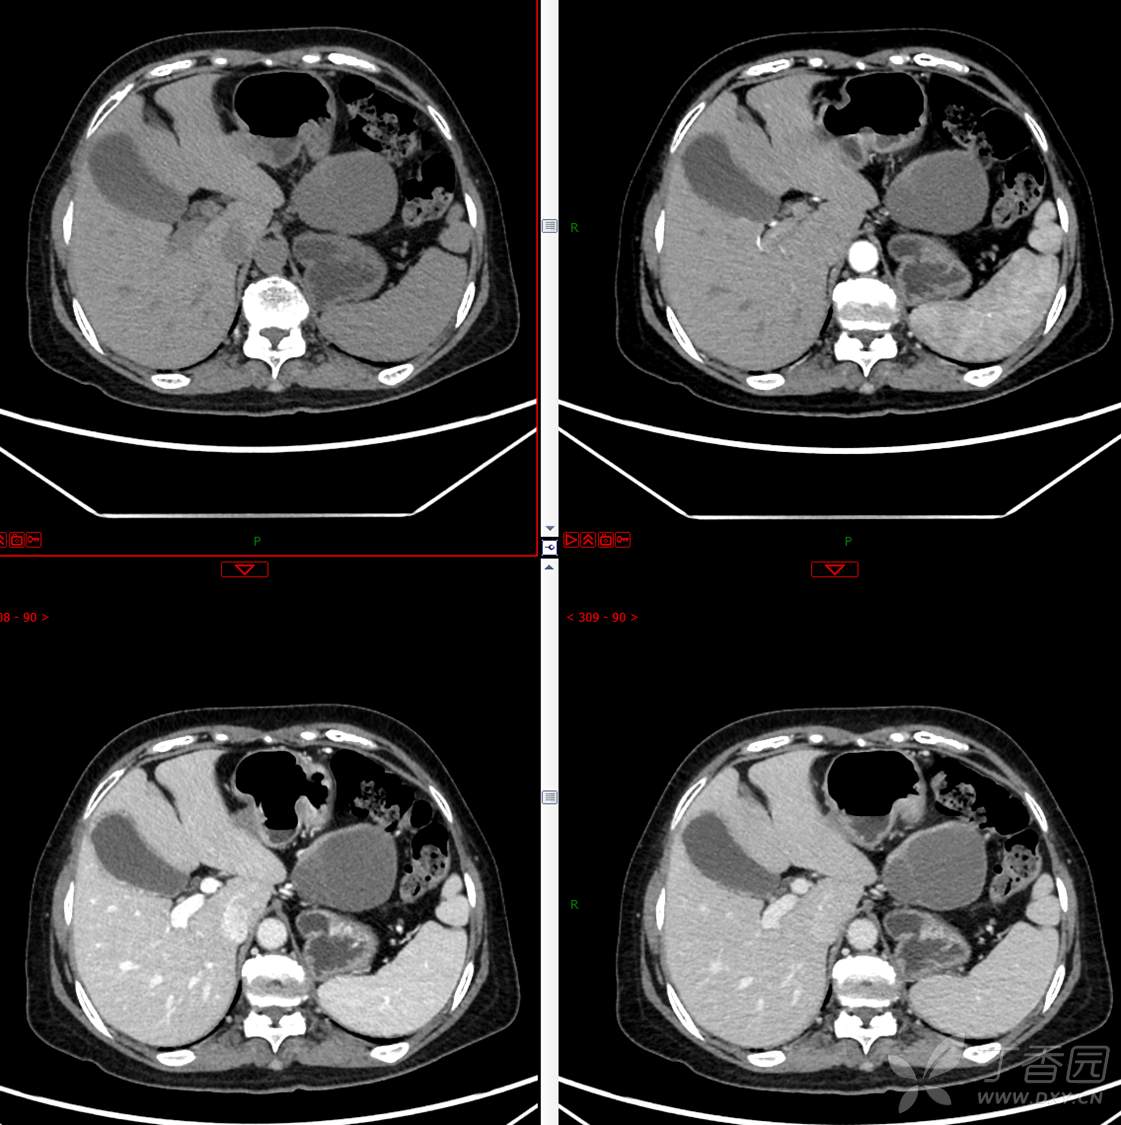

主 诉:发现胰腺占位性病变3月

现病史:患者3月前就诊于**市人民医院行腹部增强CT发现胰尾占位性病变,无腹痛、腹胀,无恶心呕吐,无黄疸,无呕血黑便,无胸闷憋气,无寒战高热,未行特殊治疗